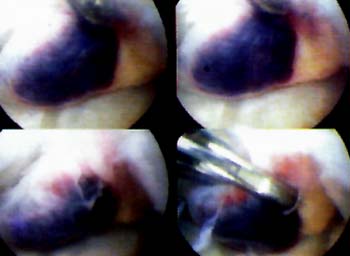

La imagen artrosc6pica nos demuestra su coloracion rojiza y de aspecto vesicular semejante a "racimos de uva" (Figura 5)

Fig. 5: Hemangioma Vascular Vesicular de rodilla

Fig. 6: Hemangioma Vascular Nodular de rodilla

En este estudio se comprueba la aparici6n de un tumor vascular nodular ubicado delante del LCP. (Figura 6)

En el primero de los pacientes el tumor fue facilmente localizado por su coloracion rojoviolacea y se destaca su aspecto vesicular y multilobulado adoptando la clasica forma en "racimos de uvas". (Fig. 5)

En el segundo caso el aspecto del tumor lo era en forma nodular su coloracion rojovinosa y su ubicacion por delante del LCP. (Fig. 6)